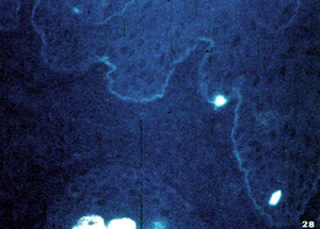

Ésta también es una enfermedad  autoirnmune. En esta enfermedad el cuerpo produce  anticuerpos en contra de la basal. Por consiguiente, el diagnóstico puede hacerse por  inmunofluorescencia. La inmunofluorescencia directa en el material de la biopsia generalmente se prefiere a los estudios del suero.

En esta microfotografía el  modelo fluorescente sigue la membrana basal y esto es diagnóstico de enfermedad.